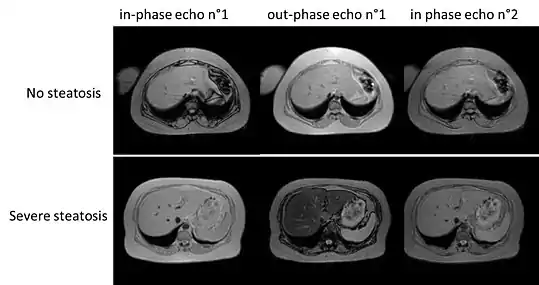

Imaging

A liver ultrasound scan or magnetic resonance imaging (MRI) can diagnose steatosis,[69] but not fibrosis and confirmation of early cirrhosis detection by ultrasound by other diagnostic methods is recommended.[66] The European Association for the Study of the Liver (EASL) recommends screening for steatosis whenever NAFLD is suspected as this is a strong predictor of the disease evolution and predicts future type 2 diabetes, cardiovascular events, and hypertension.[16] These non-invasive methods can be used for NAFLD screening but are not accepted as a substitute for liver biopsy in NAFLD nor NASH clinical trials, as only a liver biopsy can define liver pathology.[7][14]

Ultrasound presented average sensitivity and specificity for diagnosing the disease in children, while in the adult population, sensitivity and specificity were significantly higher. Proton density fat fraction magnetic resonance imaging has been increasingly used for the diagnosis of steatosis in pediatric patients.

Computerized tomography and magnetic resonance imaging are more accurate in detecting cirrhosis than conventional ultrasound.[66] Transient elastography is recommended for the initial assessment of liver fibrosis and cirrhosis and helps to predict complications and prognosis, but the interpretation of results is carefully weighed in the presence of limiting factors such as steatosis, high BMI, low amount of hepatic fibrosis, narrow spaces between the ribs, and portal hypertension. Transient elastography is not a substitute for liver biopsy.[66]

Magnetic resonance elastography (MRE) is an established method that can accurately assess hepatic fibrosis and is recommended by the APASL, AGA, ACR and AASLD.[66] MRE possesses excellent accuracy to detect fibrosis in NAFLD regardless of BMI and inflammation, and is suggested as a more reliable alternative to diagnose NAFLD and its progression to NASH compared to ultrasound and blood tests.[27][32][71][72]